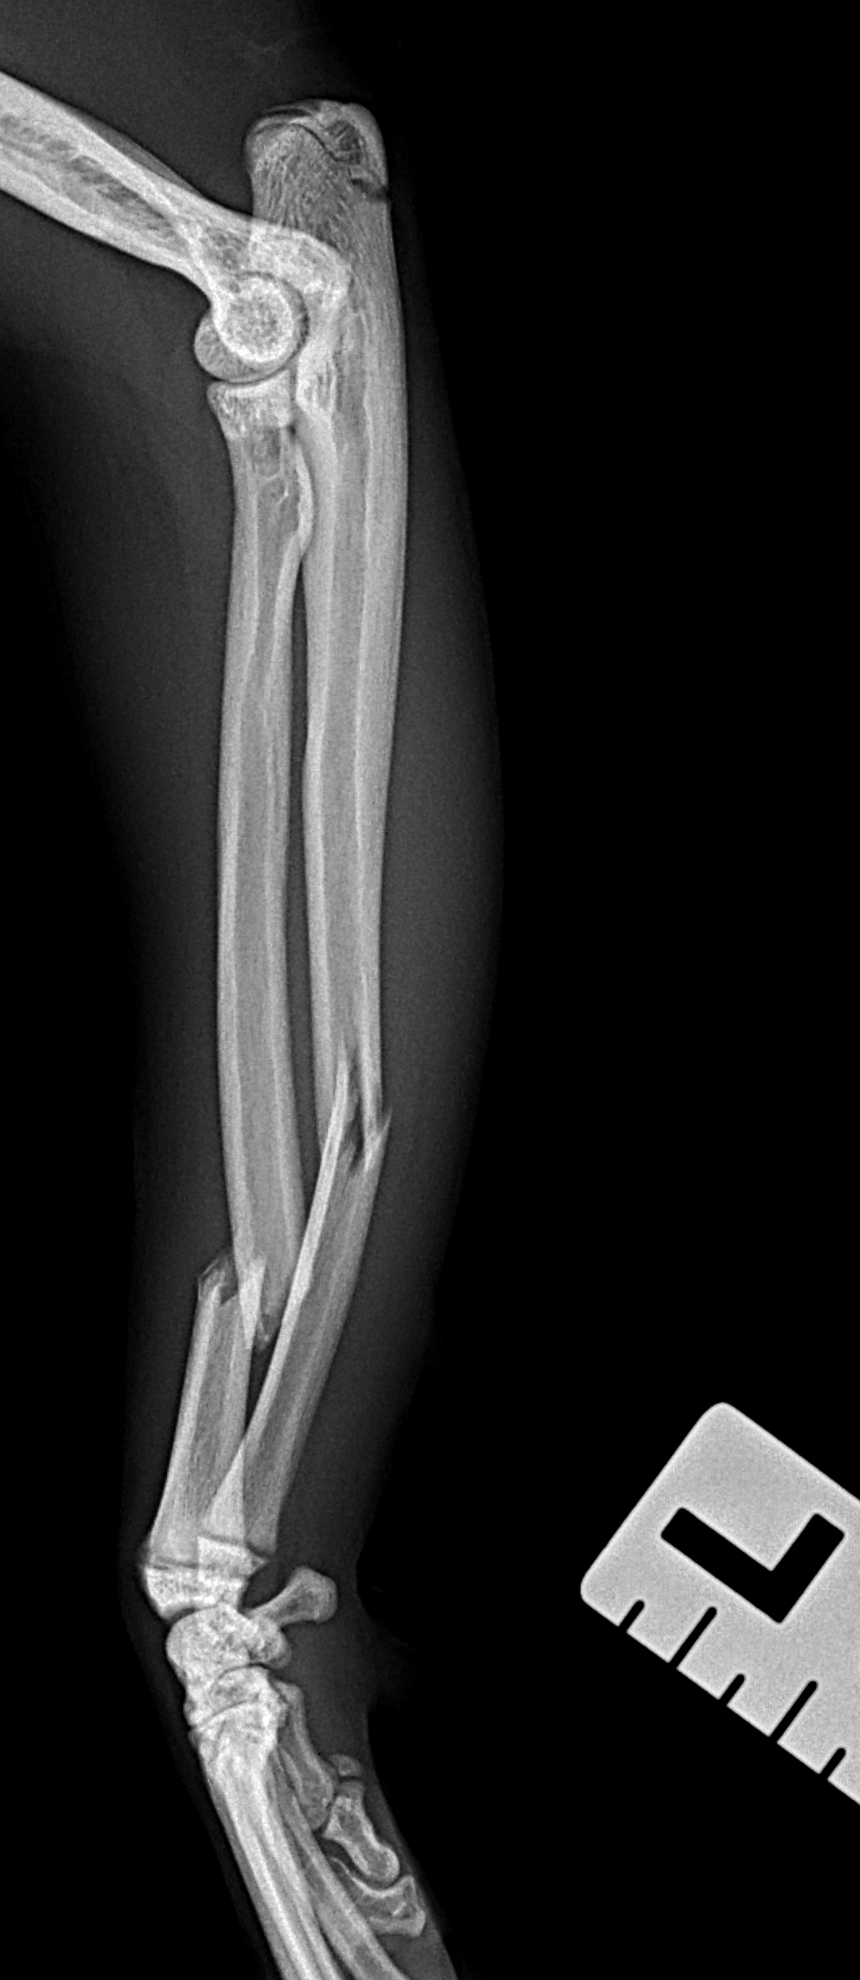

猫さんがご自宅の2Fから落下したとのことで、かかりつけ医を受診されました。右の橈骨尺骨骨折が確認されました。2.4 Titnium Locking Plate(Distal 3holeストレート)、尺骨1.6mm Titanium Wireで固定術を行いました。猫は高いところで遊ぶのが好きな動物なので、遊び場に危険な場所がないか?生活環境を見直す必要があります。